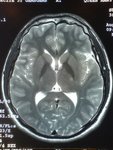

RadioEdric :: 我是白老鼠廿幾號 - 瑪麗醫院新裝之 3T 磁力共振掃瞄器